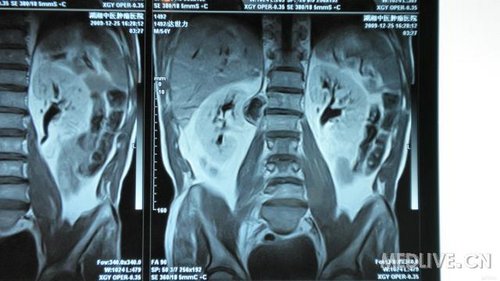

串者因腰椎间盘突出入院治疗,但询问病史查体时发现患者近1月来出现右腹股沟处麻木,局部感觉减退。做MRI等检查发现L1、2处椎管肿瘤。准备行手术治疗,但患者经济困难。各位专家指点一下选什么手术入路对脊柱稳定性影响比较小,尽量不上内固守。

还有MRI片

还有MRI片.